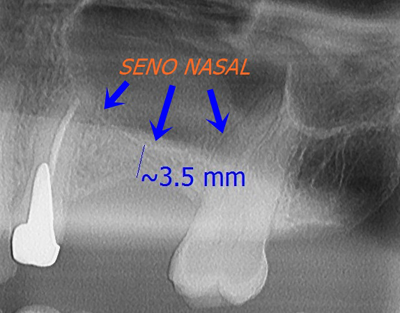

Tras realizar al paciente una radiografía panorámica y un scaner o tac dental, constatamos que tenía solamente entre 2- 3 mm de altura ósea por lo que debemos hacer una elevación de seno para que los implantes puedan tener suficiente hueso donde fijarse.